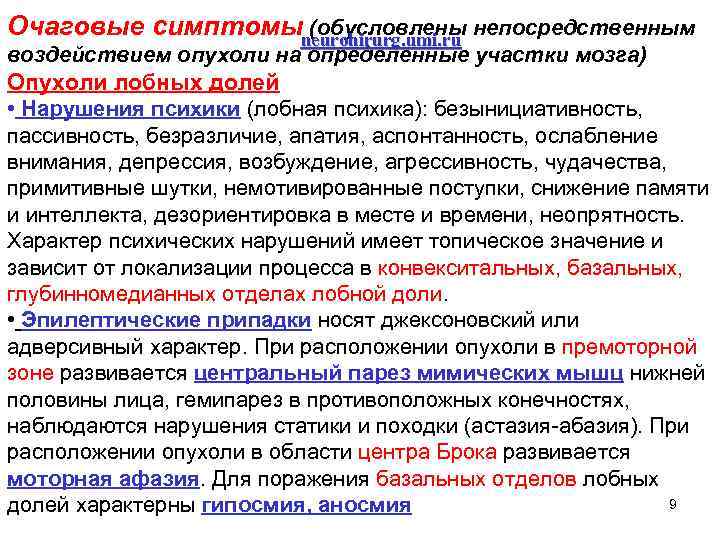

Очаговые симптомыneurohirurg. umi. ru (обусловлены непосредственным воздействием опухоли на определенные участки мозга) Опухоли лобных долей • Нарушения психики (лобная психика): безынициативность, пассивность, безразличие, апатия, аспонтанность, ослабление внимания, депрессия, возбуждение, агрессивность, чудачества, примитивные шутки, немотивированные поступки, снижение памяти и интеллекта, дезориентировка в месте и времени, неопрятность. Характер психических нарушений имеет топическое значение и зависит от локализации процесса в конвекситальных, базальных, глубинномедианных отделах лобной доли. • Эпилептические припадки носят джексоновский или адверсивный характер. При расположении опухоли в премоторной зоне развивается центральный парез мимических мышц нижней половины лица, гемипарез в противоположных конечностях, наблюдаются нарушения статики и походки (астазия-абазия). При расположении опухоли в области центра Брока развивается моторная афазия. Для поражения базальных отделов лобных 9 долей характерны гипосмия, аносмия